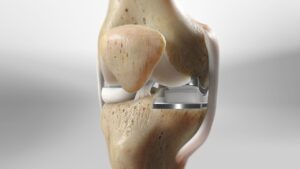

Partial knee replacement (PKR), also known as unicondylar or unicompartmental knee replacement, is a surgical procedure that replaces only the damaged portion of the knee joint, while preserving the healthy parts. Unlike total knee replacement, PKR focuses on restoring function by targeting one or two specific compartments of the knee.